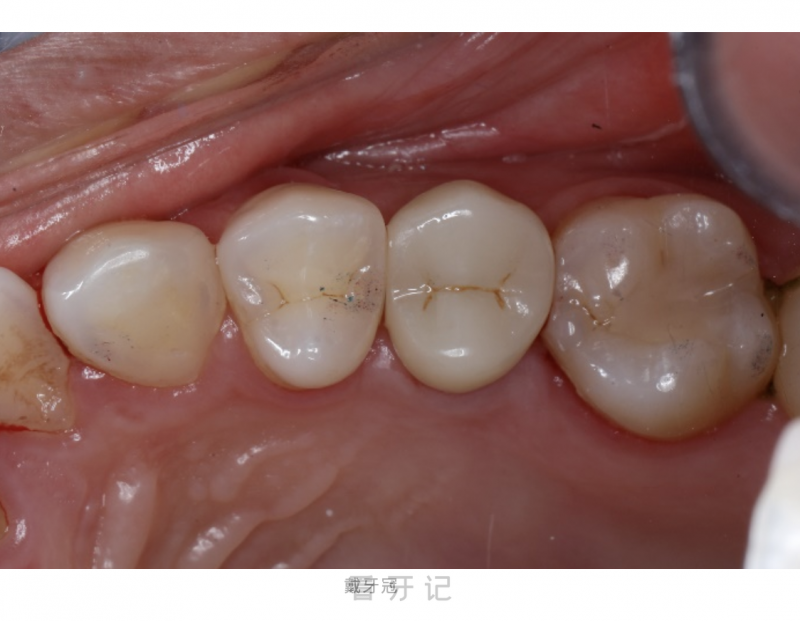

第3次就诊:戴牙冠。

医生会将定制完成的全瓷冠修复体精准就位,适度调整后粘接固定。全瓷冠具有出色的美观性,其色泽和形态与天然牙高度相似,同时具备良好的生物相容性和耐磨性,能够有效恢复牙齿的咀嚼功能。